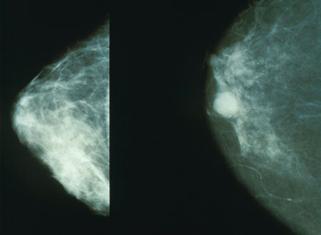

Elem care sugereaza un cc : opacitate cu contur difuz, spiculi, microcalcificari, edem peritumoral (halou transparent), ingrosarea lizereului cutanat

Fig. nr. 4 Mamografii (normal- stg, cancer- dr)